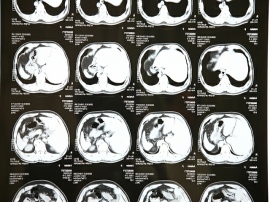

この共同研究では、胸部X線写真を用いた新型コロナウイルス肺炎罹患状況を判定するAIや血液検査や病歴などの診療情報に基づき重症化を予測するAI、またこのデータをもとに看護師の業務量をAIで数値化し、病床移動スケジュールも含め幅広くその有効性を検証する。この共同研究によって医療分野におけるDXを進め、医師の診療や看護師の配置計画、病床管理など総合的に医療現場を支援するとともに、コロナ禍における安定的かつ継続的な病院経営への貢献を目指す。